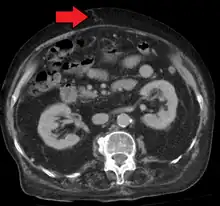

In addition, a widened (dilated) portal vein as seen on a CT scan or MRI may raise the suspicion about portal hypertension. A cutoff value of 13 mm is widely used in this regard, but the diameter is often larger than this is in normal individuals as well.[9]

Mark.png)

Ultrasonography (US) is the first-line imaging technique for the diagnosis and follow-up of portal hypertension because it is non-invasive, low-cost and can be performed on-site.[17]

A dilated portal vein (diameter of greater than 13 or 15 mm) is a sign of portal hypertension, with a sensitivity estimated at 12.5% or 40%.[18] On Doppler ultrasonography, a slow velocity of <16 cm/s in addition to dilatation in the main portal vein are diagnostic of portal hypertension.[19] Other signs of portal hypertension on ultrasound include a portal flow mean velocity of less than 12 cm/s, porto–systemic collateral veins (patent paraumbilical vein, spleno–renal collaterals and dilated left and short gastric veins), splenomegaly and signs of cirrhosis (including nodularity of the liver surface).[17]

The hepatic venous pressure gradient (HVPG) measurement has been accepted as the gold standard for assessing the severity of portal hypertension. Portal hypertension is defined as HVPG greater than or equal to 5 mmHg and is considered to be clinically significant when HVPG exceeds 10 to 12 mmHg.[20]